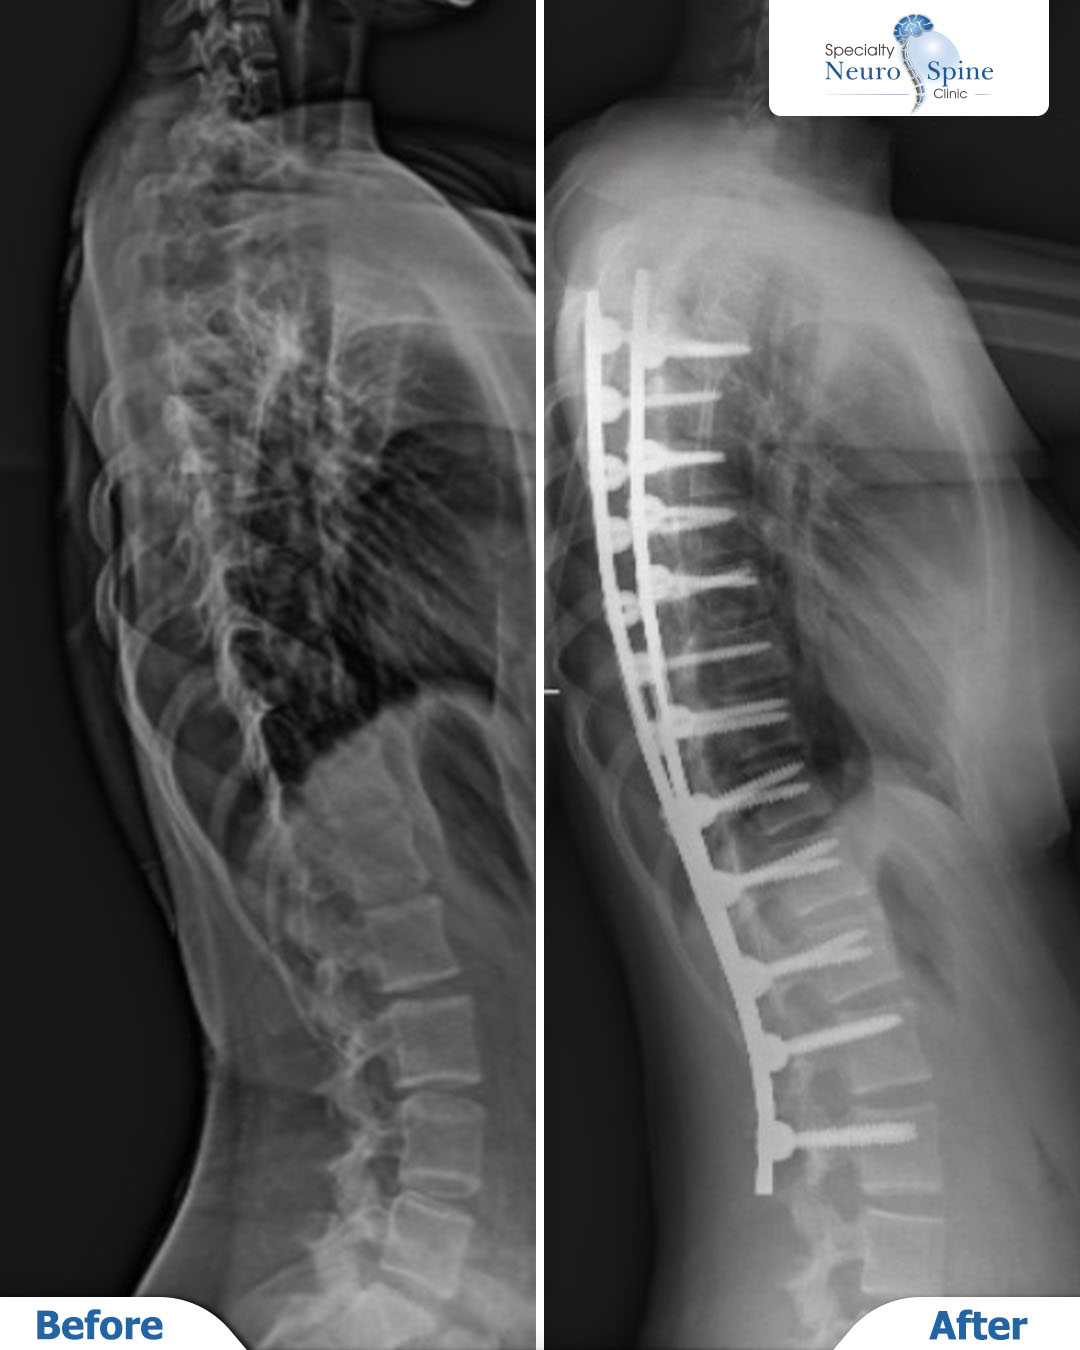

من زيارة مريضتنا الغالية مريم، 14 عاماً من الأردن، بعد شهر من عملية تصحيح انحراف العمود الفقري بالتدخل الجراحي المحدود.

بدأت المشي في اليوم التالي للعملية، وبعد شهر واحد فقط كانت قد عادت إلى ممارسة حياتها اليومية بشكل كامل.

رحلة قصيرة لكنها فارقة، تعكس أهمية التدخل في الوقت المناسب، والنتائج التي يحققها الدكتور فراس الحُسبان لمرضاه.